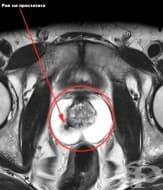

ЯМР на таз

Ядрено магнитния резонанс на таза е нерентгенов метод за послойно изобразяване на органите и структу...